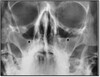

What pathology is seen here? What projection is this?

-Sinusitis -Waters sinus method

193

What are the radiographic appearances of sinusitis in CT?

1. See fluid posteriorly in CT 2. Increased thickening of the walls 3. Airway inflamed

194